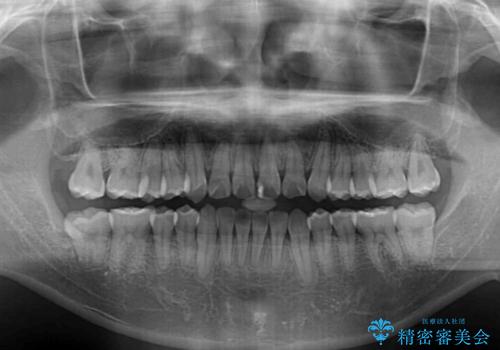

- 上下のデコボコと前歯のクロスバイトを改善したいとのことで来院された患者様です。

マウスピース矯正での自己管理には自信がないとのことで、ワイヤー装置による矯正治療を行うこととしました。

デコボコの程度は強かったのですが、口元の突出感はなかったため、非抜歯矯正としました。